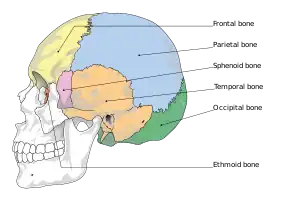

The human skull is anatomically divided into two parts: the neurocranium, formed by eight cranial bones that houses and protect the brain—and the facial skeleton (viscerocranium) composed of fourteen bones, not including the three ossicles of the inner ear.[22] The term skull fracture typically means fractures to the neurocranium, while fractures of the facial portion of the skull are facial fractures, or if the jaw is fractured, a mandibular fracture.[23]

The eight cranial bones are separated by sutures : one frontal bone, two parietal bones, two temporal bones, one occipital bone, one sphenoid bone, and one ethmoid bone.[24]

Skull thickness is variable, depending on location. Thus the traumatic impact required to cause a fracture depends on the impact site. The skull is thick at the glabella, the external occipital protuberance, the mastoid processes, and the external angular process of the frontal bone. Areas of the skull that are covered with muscle have no underlying diploë formation between the internal and external lamina, which results in thin bone more susceptible to fractures.

Skull fractures occur more easily at the thin squamous temporal and parietal bones, the sphenoid sinus, the foramen magnum (the opening at the base of the skull that the spinal cord passes through), the petrous temporal ridge, and the inner portions of the sphenoid wings at the base of the skull. The middle cranial fossa, a depression at the base of the cranial cavity forms the thinnest part of the skull and is thus the weakest part. This area of the cranial floor is weakened further by the presence of multiple foramina; as a result this section is at higher risk for basilar skull fractures to occur. Other areas more susceptible to fractures are the cribriform plate, the roof of orbits in the anterior cranial fossa, and the areas between the mastoid and dural sinuses in the posterior cranial fossa.[26]